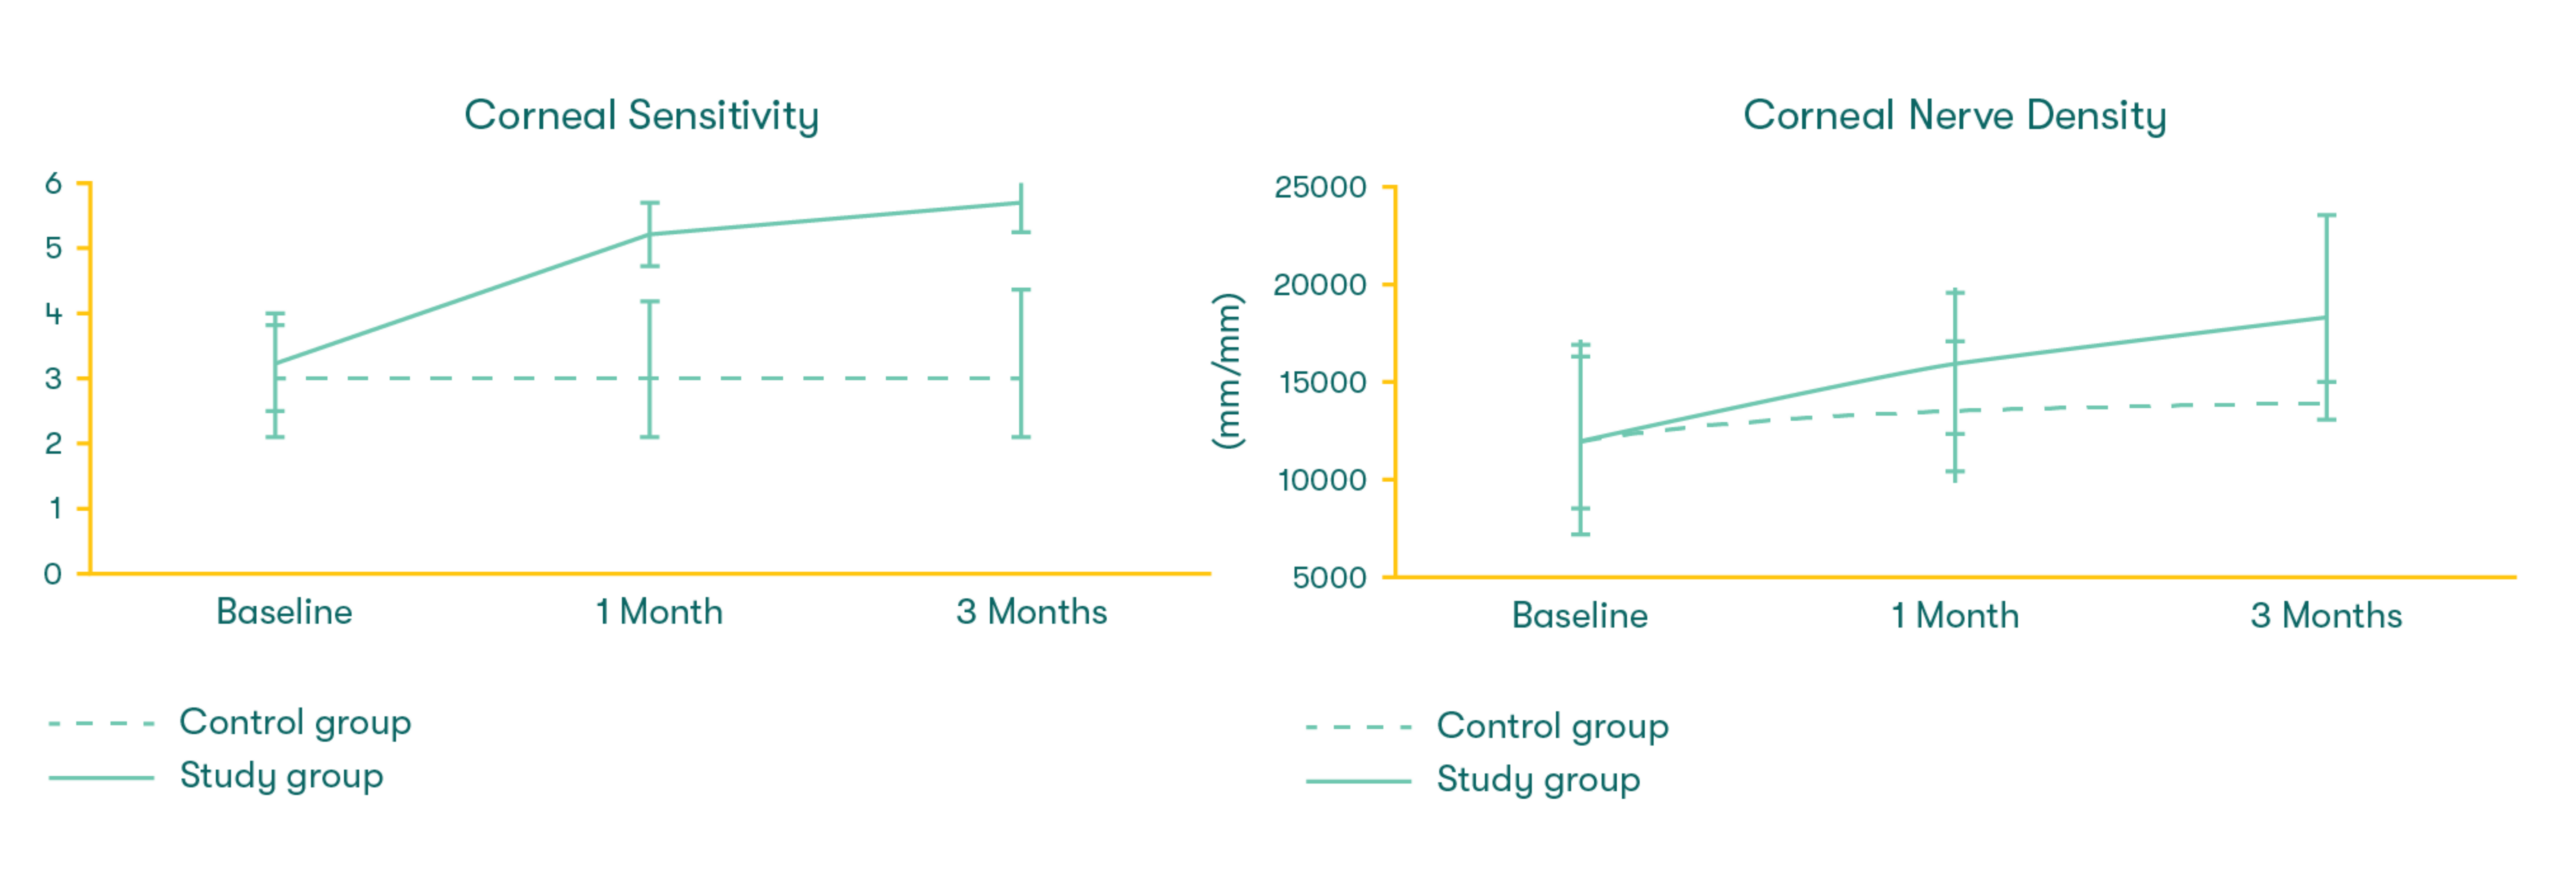

As featured in Thomas John’s clinical study, there was a significant increase in corneal sensitivity from 1 to 3 months. This improvement was significantly correlated with the increase of corneal nerve density.7

CAM preserves innate complexes found in amniotic membrane tissue that help support the regeneration of corneal surface.8,9 In a clinical study, CAM is shown to reduce signs and symptoms in ocular surface disease and restore corneal nerve density, helping improve corneal sensitivity in patients with Dry Eye Disease. 7